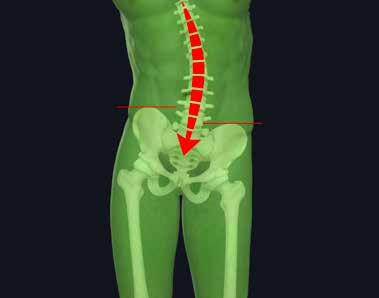

La Bio-Ortodonzia studia la corretta crescita dell’arcata mascellare e mandibolare durante la loro evoluzione. Tale interrelazione è il risultato di un complesso processo dinamico che si esplica dall’infanzia all’età adulta mediante fisiologici cambiamenti, maggiormente evidenti in alcune fasi della dentizione rispetto ad altre; il tutto è correlato alla modalità di crescita delle strutture scheletriche, alle influenze ambientali e al processo di formazione ed eruzione degli elementi dentali. Dalle evidenze scientifiche e cliniche oggi sappiamo che l’equilibrio muscolo-scheletrico dell’apparato stomatognatico condiziona anche l’equilibrio muscolo-scheletrico dell’intero corpo del paziente, in altre parole i disturbi funzionali dell’occlusione, dell’articolazione temporo-mandibolare e dei muscoli masticatori possono provocare disfunzioni in distretti diversi dell’organismo, lontani dalla bocca come la testa, la zona cervicale, la schiena, il bacino, gli arti inferiori e il piede.

Dalle evidenze, scientifca e clinica, oggi sappiamo che l’equilibrio muscolo-scheletrico dell’apparato stomatognatico condiziona anche l’equilibrio muscolo-scheletrico dell’intero corpo del paziente. In altre parole, i disturbi funzionali dell’occlusione, dell’articolazione temporo-mandibolare e dei muscoli masticatori possono provocare disfunzioni in distretti diversi dell’organismo, anche lontani dalla bocca come la testa, la zona cervicale, la schiena, il bacino, gli arti inferiori e il piede. Questi disturbi, in molti casi, sono responsabili di una sintomatologia così dolorosa da compromettere, in parte o completamente, la qualità della vita (Vanini, Cardarelli, D’Arcangelo 2021). La relazione anatomica tra la mandibola e l’osso ioide, attraverso i muscoli sovraioidei e sottoioidei, spiega come la posizione mandibolare possa interferire e condizionare la postura segmentaria del corpo. La mandibola, infatti, infuenza la posizione dell’osso ioide attraverso i muscoli sovraioidei. I muscoli digastrico e stiloioideo vincolano la posizione dell’osso ioide a quella della mandibola e della testa; il muscolo omoioideo, a sua volta, inserendosi sul margine superiore della scapola all’interno

48,49 _ Analisi delle creste iliache: rappresentazione grafica dell’allineamento e del disallineamento.